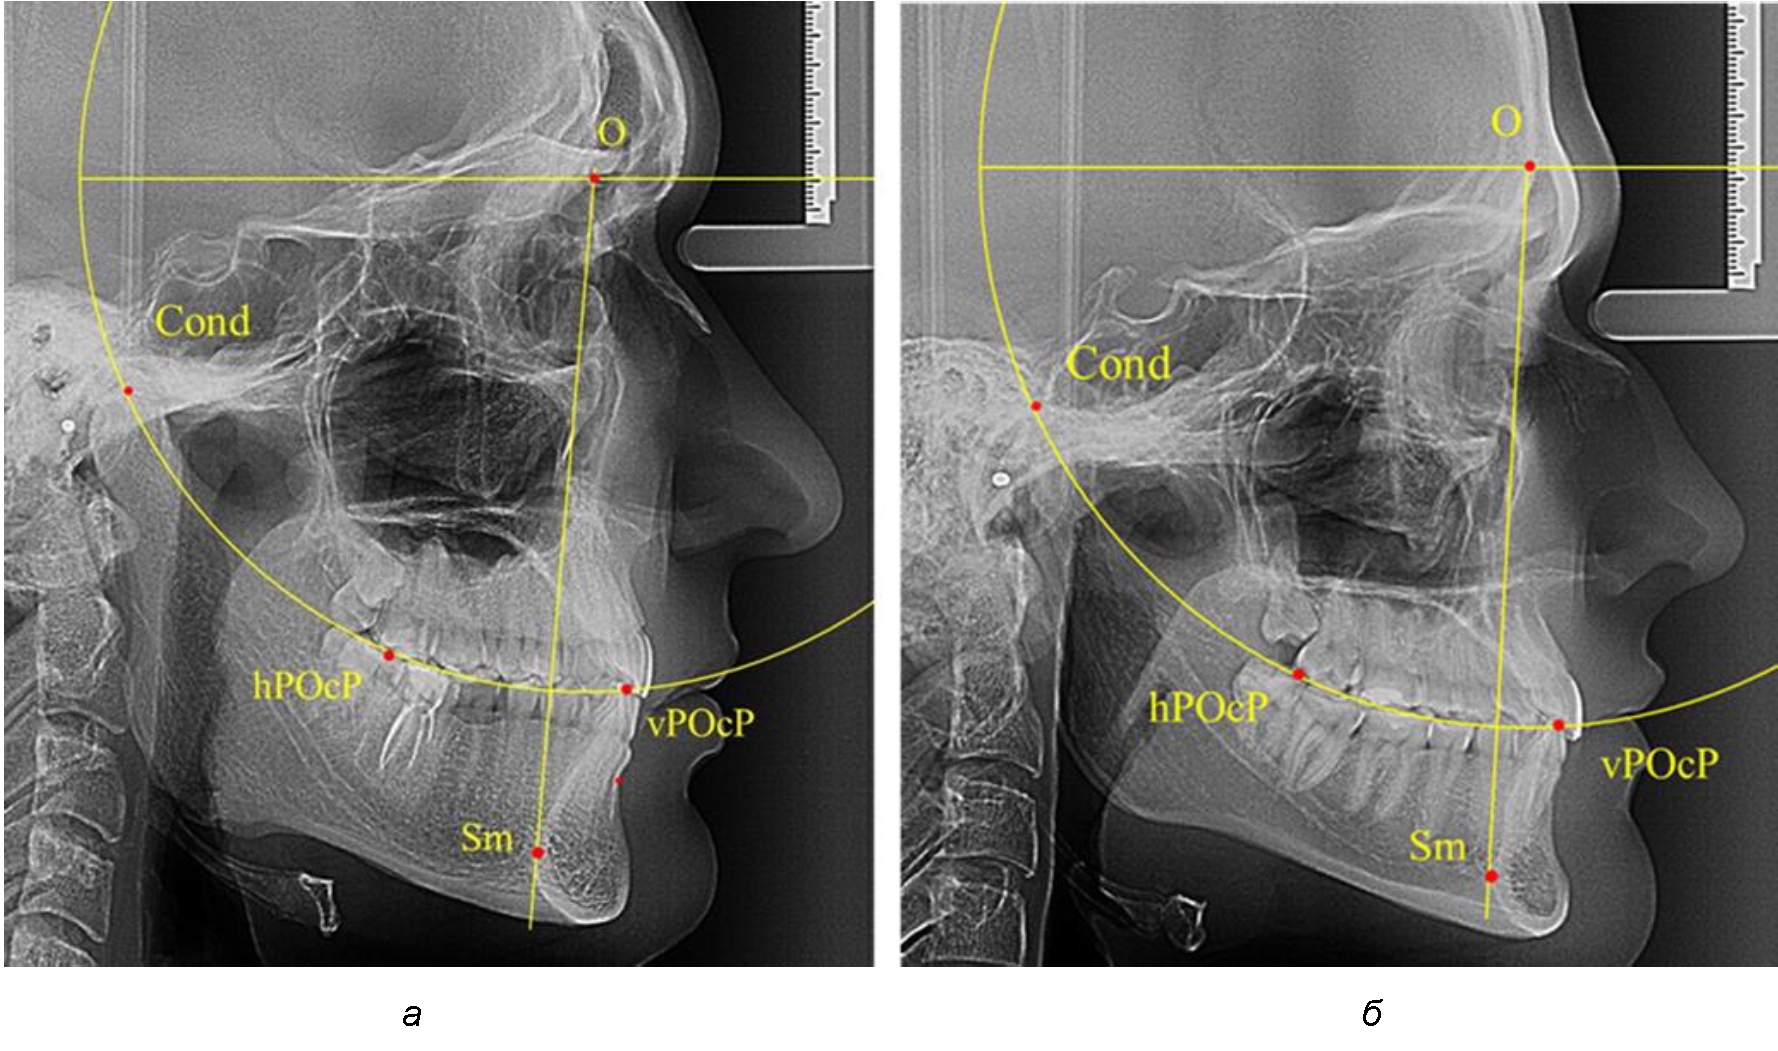

В группе рентгенограмм с ретрузионным положением резцов также проводилось распределение на подгруппы с учетом широтных размеров подбородочного выступа.

Анализ результатов показал, что практически при всех вариантах подбородочного выступа в данной группе исследования первые премоляры, как правило, располагались либо на стресс-оси Bimler, либо позади. Рентгенограммы пациентов с ретрузионным положением резцов при широком и среднем варианте подбородочного выступа представлены на рис. 4.

Таким образом, для людей с ретрузионным типом зубочелюстных дуг характерно расположение первых премоляров позади стресс-оси либо на средней линии, и этот показатель не может быть использован в качестве выбора метода лечения аномалий для данной группы исследования вне зависимости от формы подбородочного выступа.

Рис. 4. Положение первых верхних премоляров при ретрузии с широкими (а) и средними (б) размерами подбородка